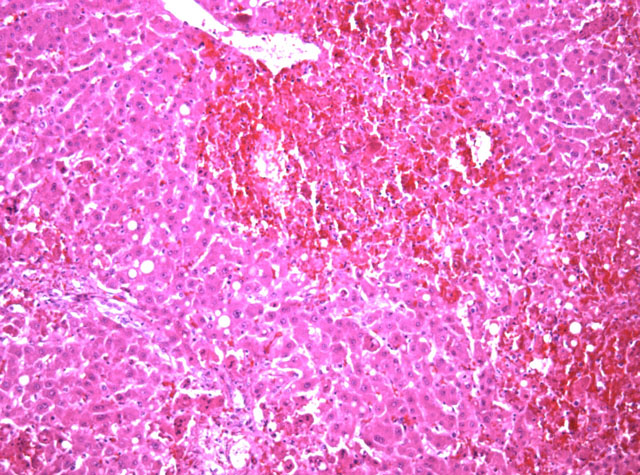

En el hígado había una extensa necrosis difusa de más del 60% del parénquima (Fig.8). La necrosis afectaba de forma aleatoria a las distintas zonas del lobulillo, con hepatocitos transformados en cuerpos eosinófilos anucleados entremezclados con hemorragia y ocasionales infiltrados neutrofílicos. Los escasos hepatocitos conservados en la periferia de las áreas necróticas presentaban inclusiones intranucleares eosinófilas y algunos eran multinucleados. Había además abundantes macrovesículas de contenido lipídico intra y extrahepatocitarias.

Fig.8 - <div style=fiogf49gjkf0dFig 8.- Necrosis hemorrágica hepática .">

Fig 8.- Necrosis hemorrágica hepática .